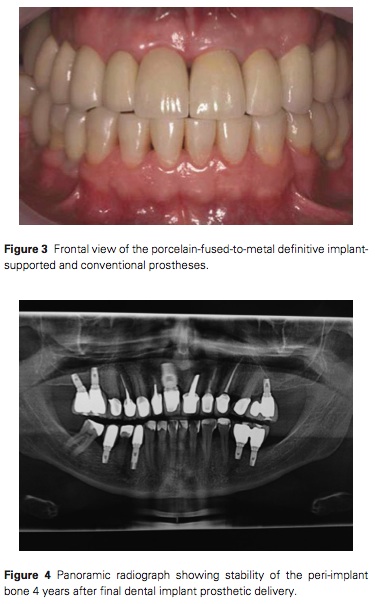

這個case提醒了我們關於Pseudo-Class III的重建過程中, 取CR以及看Ceph側顱分析的重要性. 雖然這個case運氣很好的是這患者很有錢, 缺幾顆就種幾顆. 一開始要先確認咬合, 結果在調整患者的咬合後就可以發現患者因為後牙缺失然後習慣將下顎向前移. 先用interim prosthesis去改, 然後種implant, 再改interim 4個月, 最後再給final.